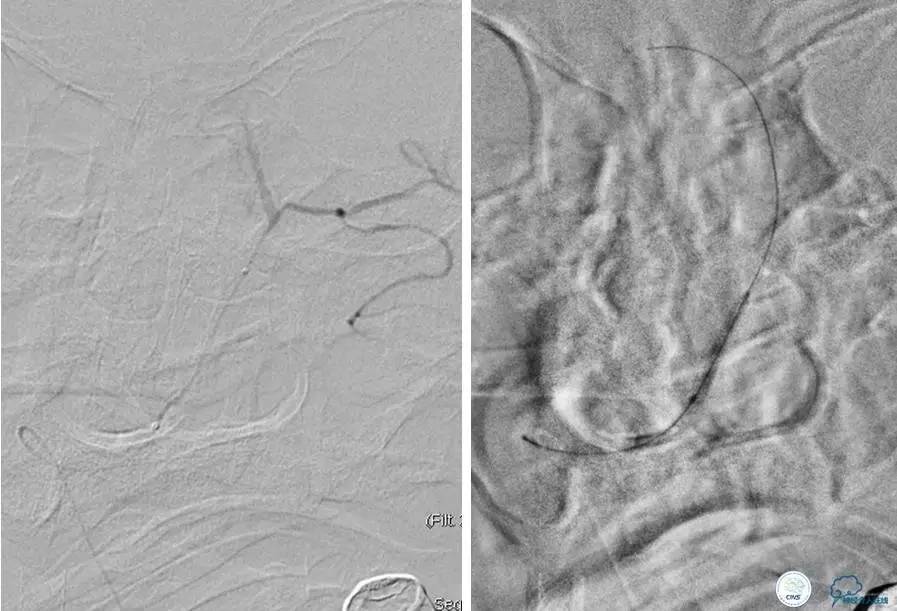

▼首先行颈动脉CTO开通术,手术顺利,Wallstent支架。

▼1周后行右侧椎动脉V4段CTO开通术。

▼微导丝穿过狭窄段,微导管造影,小球囊预扩张,2mm。

▼根据血管情况选择较大球囊再次预扩张。

▼置入2枚Wingspan支架,手术成功。

▼术后即刻CT,梗死灶内再灌注出血。

患者无症状,中性治疗。4月21日电话随访,一般情况好,当地CT示出血吸收期。